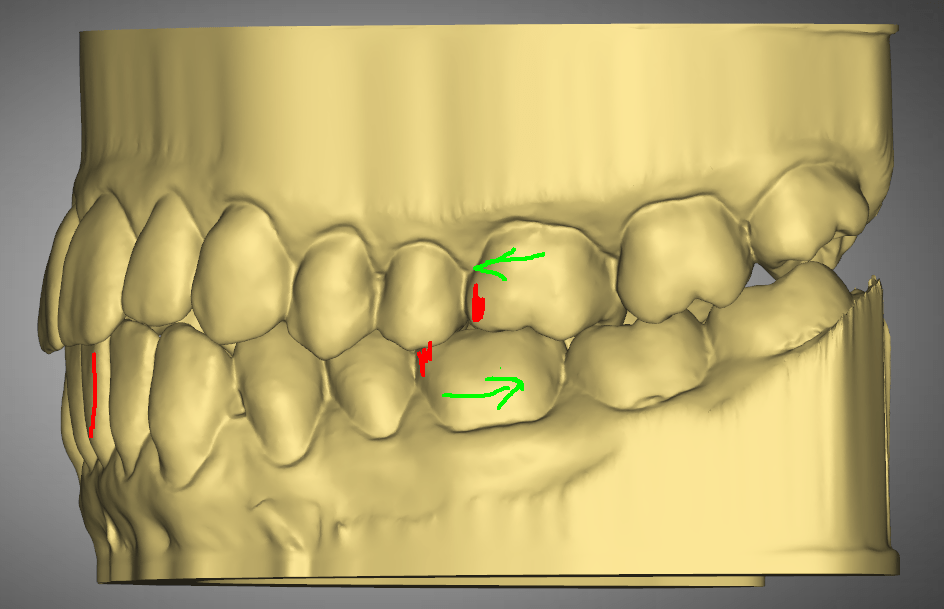

Mackenzie. L – Myobrace – Age 9

Adaptive Orthodontics TREATMENT STARTED AT AGE : 9 Myobrace K1 MediumMixed DentitionClass 2 Div IModerate 1st Review – 2023-03-01 YELLOW = Initial 2022-10-29 BLUE = 1st Review 2023-03-01 Compliance was not good in the first quarter. Not much expansion seen on buccal side 2nd Review – 2023-05-30 YELLOW = Initial 2022-10-29 BLUE = 2nd Review2023-05-30… Read.